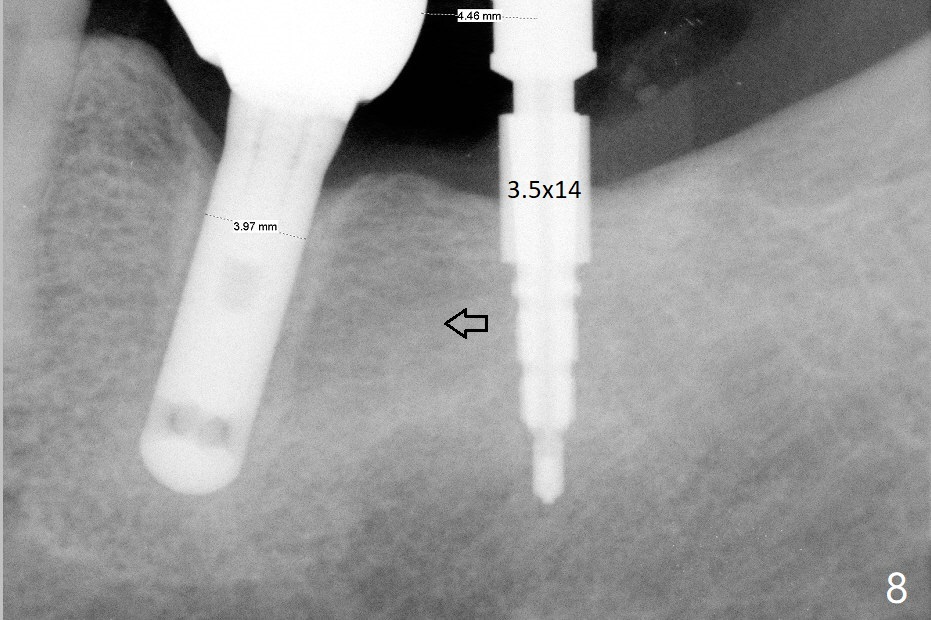

A 69-year-old man needs an implant at #18 (Fig.1,2 CT (sagittal and coronal sections)). In spite of use of surgical stent, the trajectory is not ideal (Fig.3-5). The following day the implant is removed with bone graft (Fig.6). In the 2nd placement, the trajectory is adjusted in each step (Fig.7-9 arrows) with long term stability (Fig.10,11).